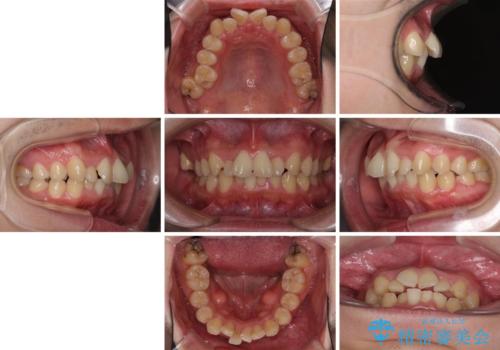

強い咬み込みですり減った前歯 デコボコを抜歯矯正で整える

- 結婚式が近いとのことで、前歯のデコボコを改善したいと来院された患者様です。

口元の突出感はないものの、上顎前歯のデコボコが著しかったため、上顎左右第一小臼歯2本を抜歯することとしました。

咬合力が非常に強く、抜歯したスペースがなかなか閉じないであろうことは予想できましたが、思っていた以上に期間がかかりました。

前歯のすり減りも著しかったため、仕上げの位置の調整にも期間を要しました。